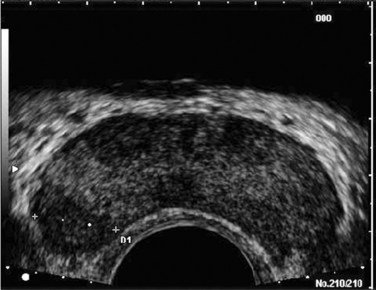

The prostatic urethra traverses the length of the gland in the midline and thus must be imaged in the sagittal plane to be simultaneously viewed along its entire course (Fig. 97–2A and B). The distended urethral lumen has a hypoechoic appearance, whereas periurethral calcifications may produce a thin echogenic outline. The smooth muscle of the internal sphincter extends from the bladder neck, encircling the urethra to the level of the verumontanum. These muscle fibers may be visualized sonographically as a hypoechoic ring around the upper prostatic urethra, giving it a funneled appearance proximally as it arises from the bladder neck. On reaching the verumontanum the urethra angles anteriorly and runs through the remainder of the gland to exit at the apex of the prostate. This angle gives the prostatic urethra an anteriorly concave appearance when viewed along its entire course in the sagittal plane.

Figure 97–2 Classic gray-scale transrectal ultrasonography imaging of the prostate. A, In the transverse plane with the hypoechoic urethra centrally located (star) and dotted line representing transverse measurement. B, Midline sagittal view with the hypoechoic urethra running the length of the gland, D1 represents longitudinal and D2 anteroposterior measurement. C, Seminal vesicles (large arrow) and vasa deferentia (small arrow) in the transverse plane.